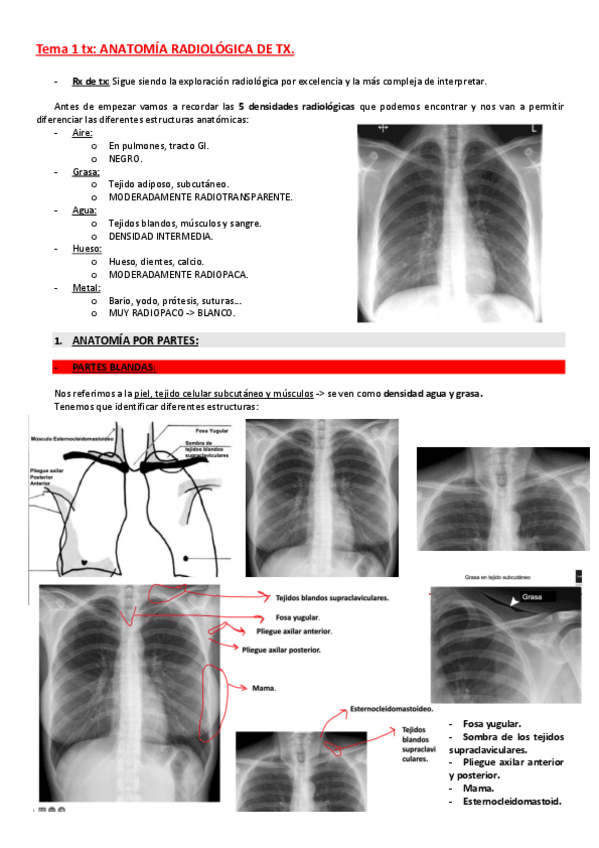

He publicado nuevos apuntes de 3º Diagnóstico por imagen: 5-TORAX.pdf

9 páginas

Tórax rayos

He publicado nuevos apuntes de 3º Diagnóstico por imagen: Tórax rayos

Torax-tema-1.pdf